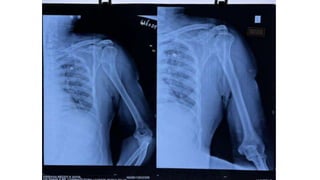

1. Xray of Left shoulder- AP , lat view

2. Xray of pelvis with both hips – Ap

• Multiple varying size cavitatory lesions along with areas of

• Left subscapular and Deltoid abcess , sclerosis of humerus

Ortho review was done i/v/o CT scan showing sclerosis of

humerus head and advised